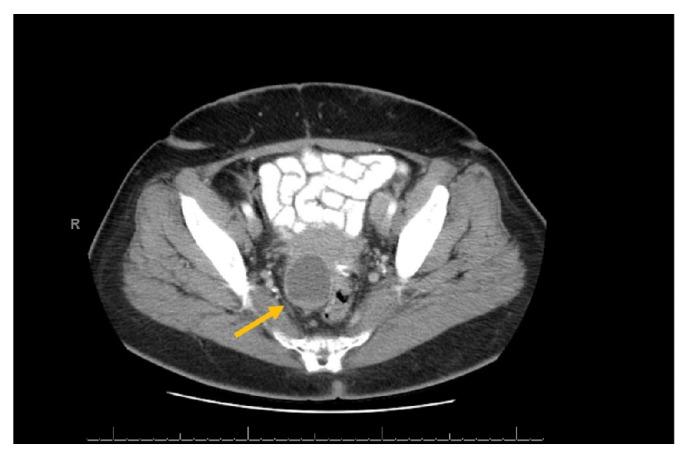

Cystic lesions located in the paravaginal region are rare. When present, paravaginal cysts are typically benign and are incidentally found on routine gynecological exams; however, rarely they can be malignant. Treatment options for paravaginal cancers are not well studied and early diagnosis may help improve prognosis in these patients. Our case describes a 55-year-old female with a recurrent paravaginal cyst that was remarkable for serous papillary adenocarcinoma despite biopsy and fluid cytology negative for malignancy. This case demonstrates that malignancy should be considered highly with a recurrent paravaginal cyst, especially when present over a short interval.

位于阴道旁区域的囊性病变很少见。阴道旁囊肿一旦出现,通常为良性,在常规妇科检查中偶然发现;然而,它们很少会发生恶变。阴道旁癌的治疗方案尚未得到充分研究,早期诊断可能有助于改善这些患者的预后。我们的病例描述了一名55岁女性,患有复发性阴道旁囊肿,尽管活检和液体细胞学检查均未发现恶性肿瘤,但最终确诊为浆液性乳头状腺癌。该病例表明,对于复发性阴道旁囊肿,尤其是在短时间内出现的囊肿,应高度怀疑恶变的可能。